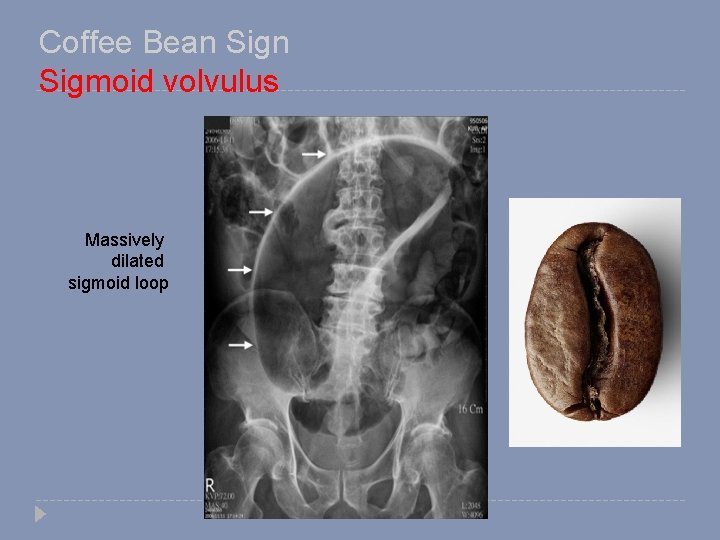

Coffee Bean Sigmoid volvulus Massively dilated sigmoid loop